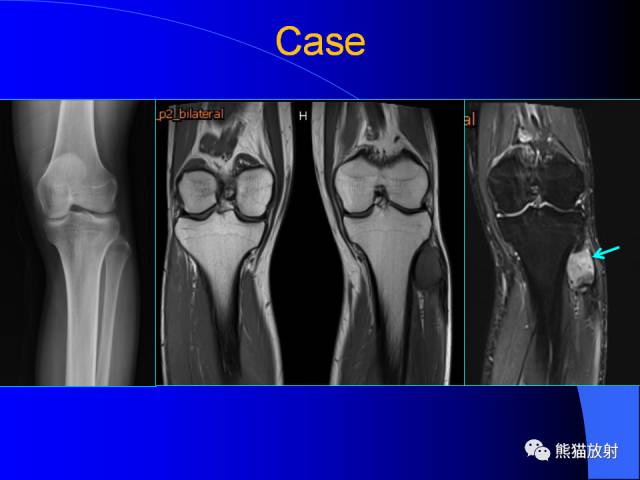

膝关节周围囊肿MRI

膝关节周围囊肿是较常见的病变,可以是原发的,多见于青年及儿童,囊内容物通常是黏液;也可以是继发的,多与关节腔相通,内含一般黏性的滑液,常继发于膝关节骨关节炎、类风湿关节炎、非特异性滑膜炎、半月板损伤、髌骨软骨软化症等。

腘窝囊肿是膝关节周围最常见的囊肿。